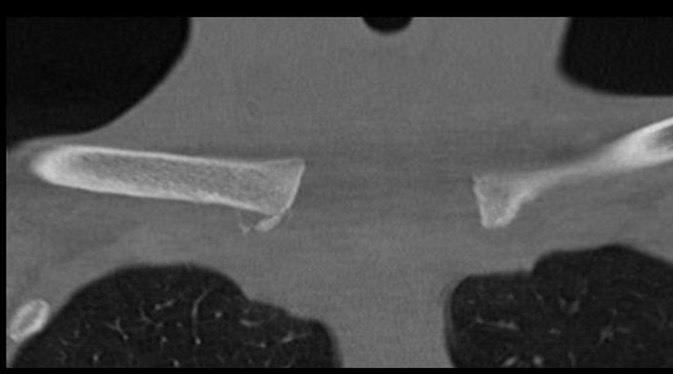

CT scan

Left posterior SCJ dislocation with pre- and post angiogram

Left posterior SCJ dislocation with pre- and post angiogram

Severe left posterior SCJ dislocation with subclavian vein compression

Condensing Osteitis

Definition

Sclerosis of the medial end of the clavicle

Does not affect the sternum

Xray

CT